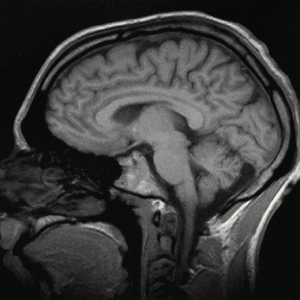

Schnitt – von (Nase) vorne |

Das am weitesten innenliegende sogenannte 'Stammhirn' (oder Hirnstamm) des Menschen, gilt als der am vielfältigsten zusammengesetzte und uneinheitlichste, der vereinfachend zusammenfassenden vier Teilbereich (so dass diese Begrifflichkeit zugunsten genauerer kleinräumlicherer Bezeichnungen verdrängt werden mag). |

Neben dem, grob gesprochen, die (teils 'bewusst', will heissen vom Menschen reflektierend bemerkt) 'denkenden' Grosshirnhälften untereinander und mit dem (die Feinmotorik des Menschen steuernden und das räumlich Gleichgewicht sichernde) Kleinhirn (Cerebellum) sowie dem (überwiegend die 'Nervensteuerung' mit der 'Hormonsteuerung' koppelnde), 'Zwischenhirn' (Diencephalon) verbindenden 'unteren, längs' Brücke (Pons), wird meist auch das (wohl Sinneseindrücke an's 'Gedächtnis' vermittelnde) 'Mittelhirn' (Mesencephalon) und die, von unten her in den Schädelraum reichende, Verlängerung des Rückenmarks (Medulla oblongata) zum Hinstamm 'gezählt' ... |

Kleinhirn (Cerebellum) bereits hälftig

(Bewegungen 'feinsteuernd') in

hinteren Schädelbereich (an GH)

angeschlossen ('sofort sichtbar')

Der eingefärbte Teil unten rechts.

Zwischenhirn (human??) mit seinen viererlei 'Talamie'

'Zwischenhirn' (Diencephalon)

quantitativ überwiegend aus

Hyothalamus(drüsen) bestehend

Thalamus (oberer Teil)

2. Hypothalamus, der mit der Hypophyse

(Hirnanhangdrüse)verbunden ist.

3. Subthalamus

4. Epithalamus

Großhirn (Cerebrum) 4/5 d.h. 85%

der Hirn-Masse aus zwei (per

'quer-Balken') verbundenen Hälften

bestehend Balken (Corpus Callosum) verbindet beide Hälften (zwischen ihnen) im Bereich des Großhirns

Es liegt über den restlichen Hirnteilen und weist viele Längs- und Querfurchen auf